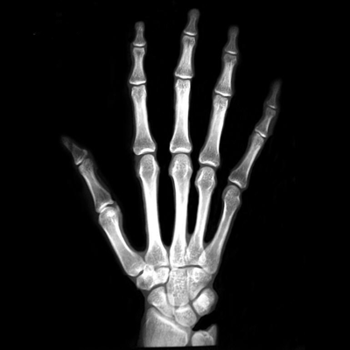

After testing our proposed method on several synthetic images, we now consider applying it on real medical images. Here, we consider a hand X-ray image as the source image (Fig. 7(a)) and a deformed hand X-ray image as the target image (Fig. 7(b)). Fig. 7(c) shows the original absolute intensity difference between the two images. It can be observed that different fingers are displaced in a nonuniform manner (for example, the displacement of the index finger is much larger than that of the little finger), while the wrist remains almost the same. Therefore, a simple rigid transformation is insufficient for yielding a good registration. As shown in Fig. 7(d), our proposed method successfully deforms the source image to match the target image, and the final intensity difference is significantly smaller (see Fig. 7(e)). From the deformed underlying grid in Fig. 7(f), it can be observed that the mapping is smooth and bijective. For comparison, both LDDMM [5] and DDemons [47] fail to register the fingers and are non-bijective (see Fig. 7(g), Fig. 7(h), and Fig. 7(i)).

We then consider another example of registering two hand X-ray images with larger deformations (see Fig. 8(a) for the source image, Fig. 8(b) for the target image, and Fig. 8(c) for their absolute intensity difference). The warped image produced by our proposed method (Fig. 8(d)) again closely resembles the target image with the intensity difference significantly reduced (see Fig. 8(e)). Fig. 8(f) shows that the mapping is smooth and bijective. For comparison, note that LDDMM [5] fails to match the fingers (Fig. 8(g)). While DROP [18] is capable of registering the fingers (Fig. 8(h)), it distorts the boundary shape of the overall image (Fig. 8(i)).